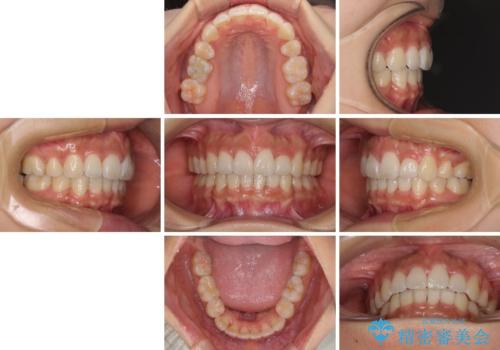

スッキリとした口元へ 出っ歯の抜歯矯正

下顎の正中を上顎に合わせる処置が難航し、期間が長引きました。

最終的には上下の正中も合い、横顔の印象が変わるほどスッキリとした口元となりました。